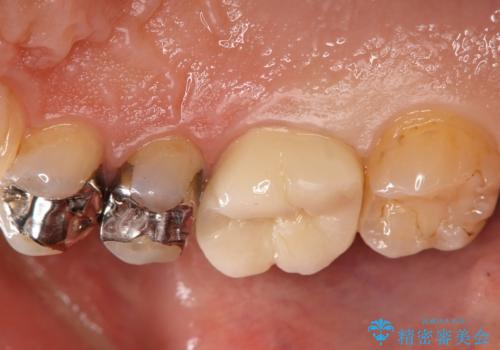

- 13.2万円費用は治療当時の料金となります

奥歯の噛み合わせが強く、治療後にセラミックが割れるリスクがあった為マウスピースの装着をして頂いてます。

他の銀歯については患者様のご希望のタイミングで治療していく予定です。